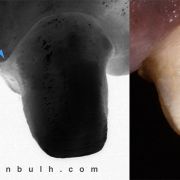

The patient was complaining of heavy stain and multiple faulty restorations. Considering the age in analyzing the teeth shape, contour and color play a vital role in success. Root canal treatment was done for the anterior teeth (Dr Khalid Merdad). Veneers and crowns @perlasmile lab.